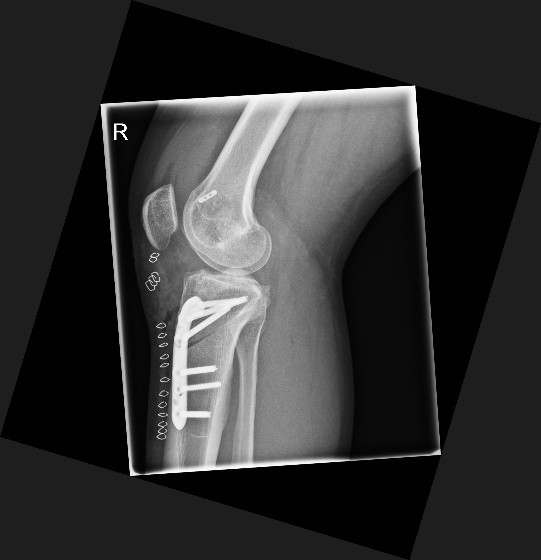

Tibiakopf Fraktur

Die arthroskopisch assistierte Frakturversorgung (insbesondere am Tibiakopf) im Rahmen von Band- bzw. Kombinationsverletzungen ist ebenfalls ein Schwerpunkt der Abteilung. Der ärztliche Direktor PD Dr. med. Schlumberger ist im DKG-Komitee „Frakturen“ vertreten.

Beinachsfehlstellungen

Manchmal liegen Beschwerden Fehlstellungen zu Grunde – sei es im Sinne eines „O-Beins“ bzw. eines „X-Beins“, aber auch eine Rotationsfehlstellung kann ursächlich für Beschwerden des Kniegelenkes sein. Gerade bei Knorpelschädigungen und Arthrose ist eine Fehlstellung mit konsekutiver Überlastung einer Gelenkhälfte oftmals ursächlich. Durch den Ausgleich der Fehlstellung wird die Biomechanik des Gelenkes wieder hergestellt und das betroffene Areal entlastet. Wir bieten Umstellungen in allen Ebenen (O-Bein, X-Bein, Rotationsfehlstellungen, pathologischer Slope, …) an. Oft ist es sogar möglich, dass eine notwendige endoprothetische Versorgung nochmals lange hinausgezögert werden kann, was vor allem jungen Patienten zu Gute kommt.